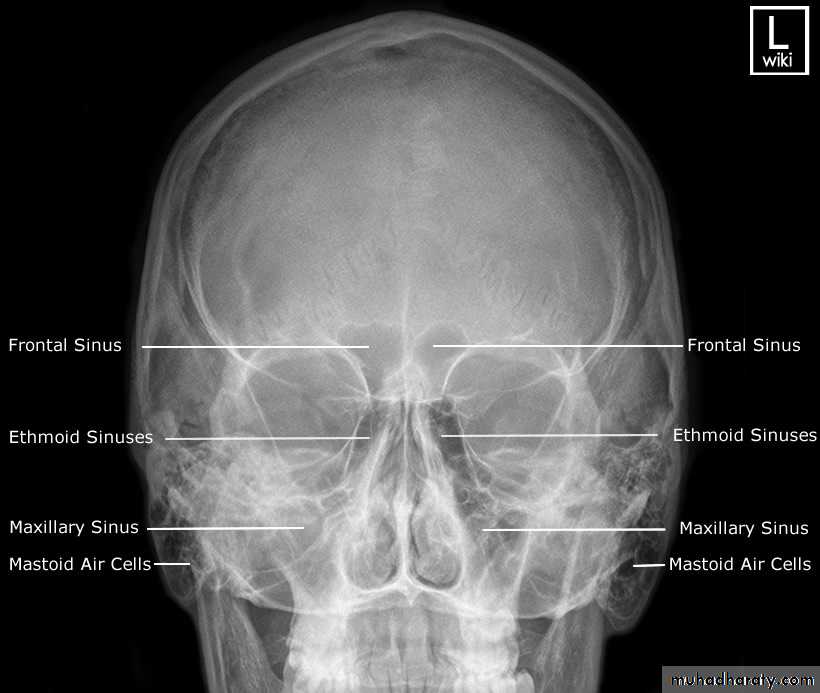

Sinuses:

• On plain radiographs the normal sinuses are transradiant because they contain air.• Plain films have a role in showing mucosal thickening, fluid levels, bone destruction and fractures.

• However, CT is often the preferred technique in sinus disease